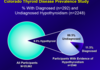

prevalence of hypothyroid

10% gen population